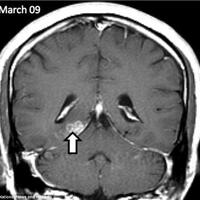

Tunggu beberapa bulan. Larvanya lagi berkembang di otak lo :takuts :recsel Cek otak lo deh. Siap tau di otaklo udah ada ginian :takuts Daripade di otak gue ada ginian, mending gue hindarin babi dan dagingnya sekalian :takuts Mencegah lebih baik daripada mengobati :recsel Kalo yang dimasak itu...